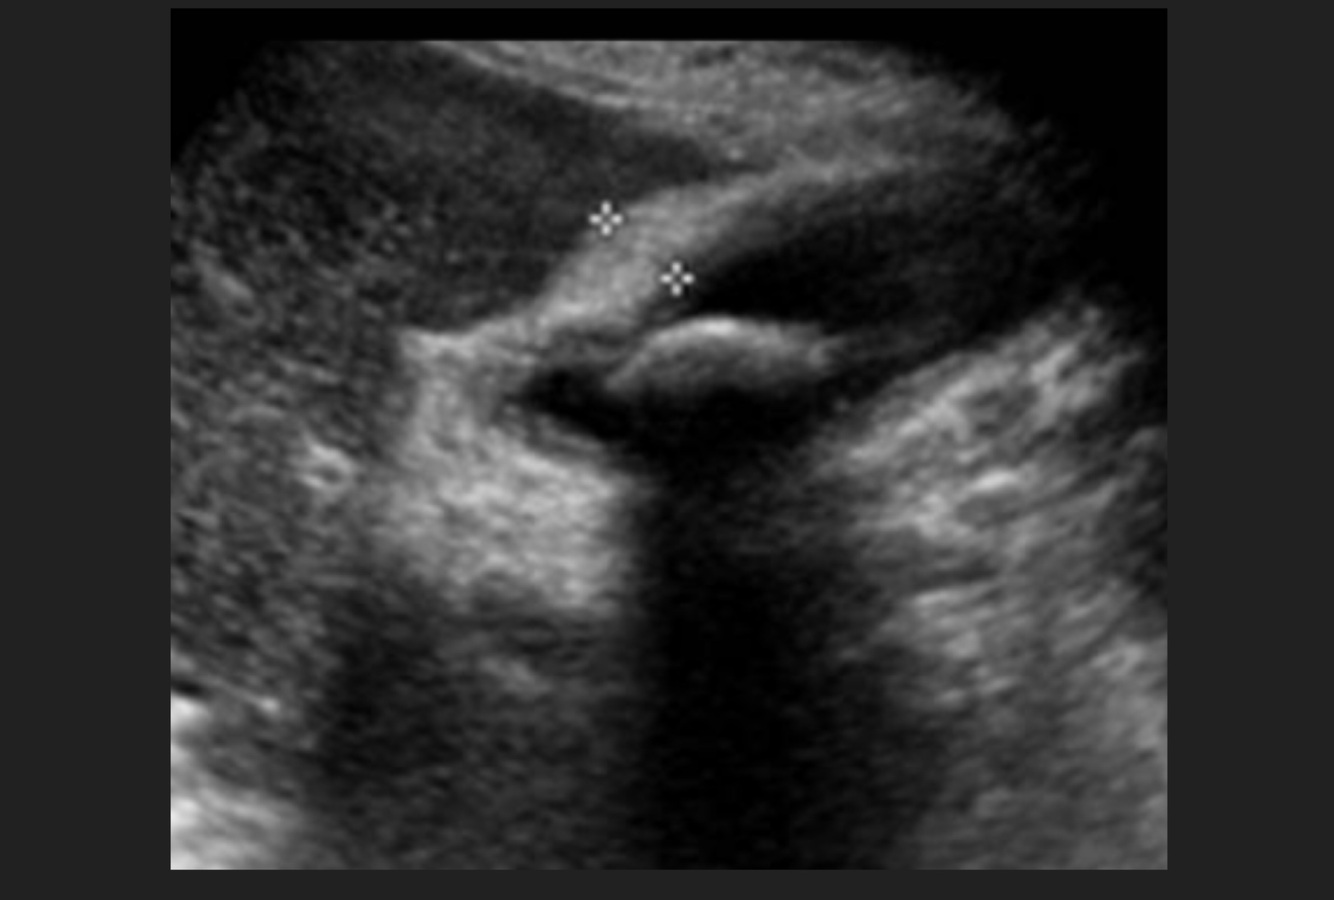

Femenino 59 años,dolor en hipocondrio derecho, vómitos, Murphy positivo, USG vesícula biliar pared 12 mm

A

Colecistitis Crónica Litiásica Agudizada (CCLA)